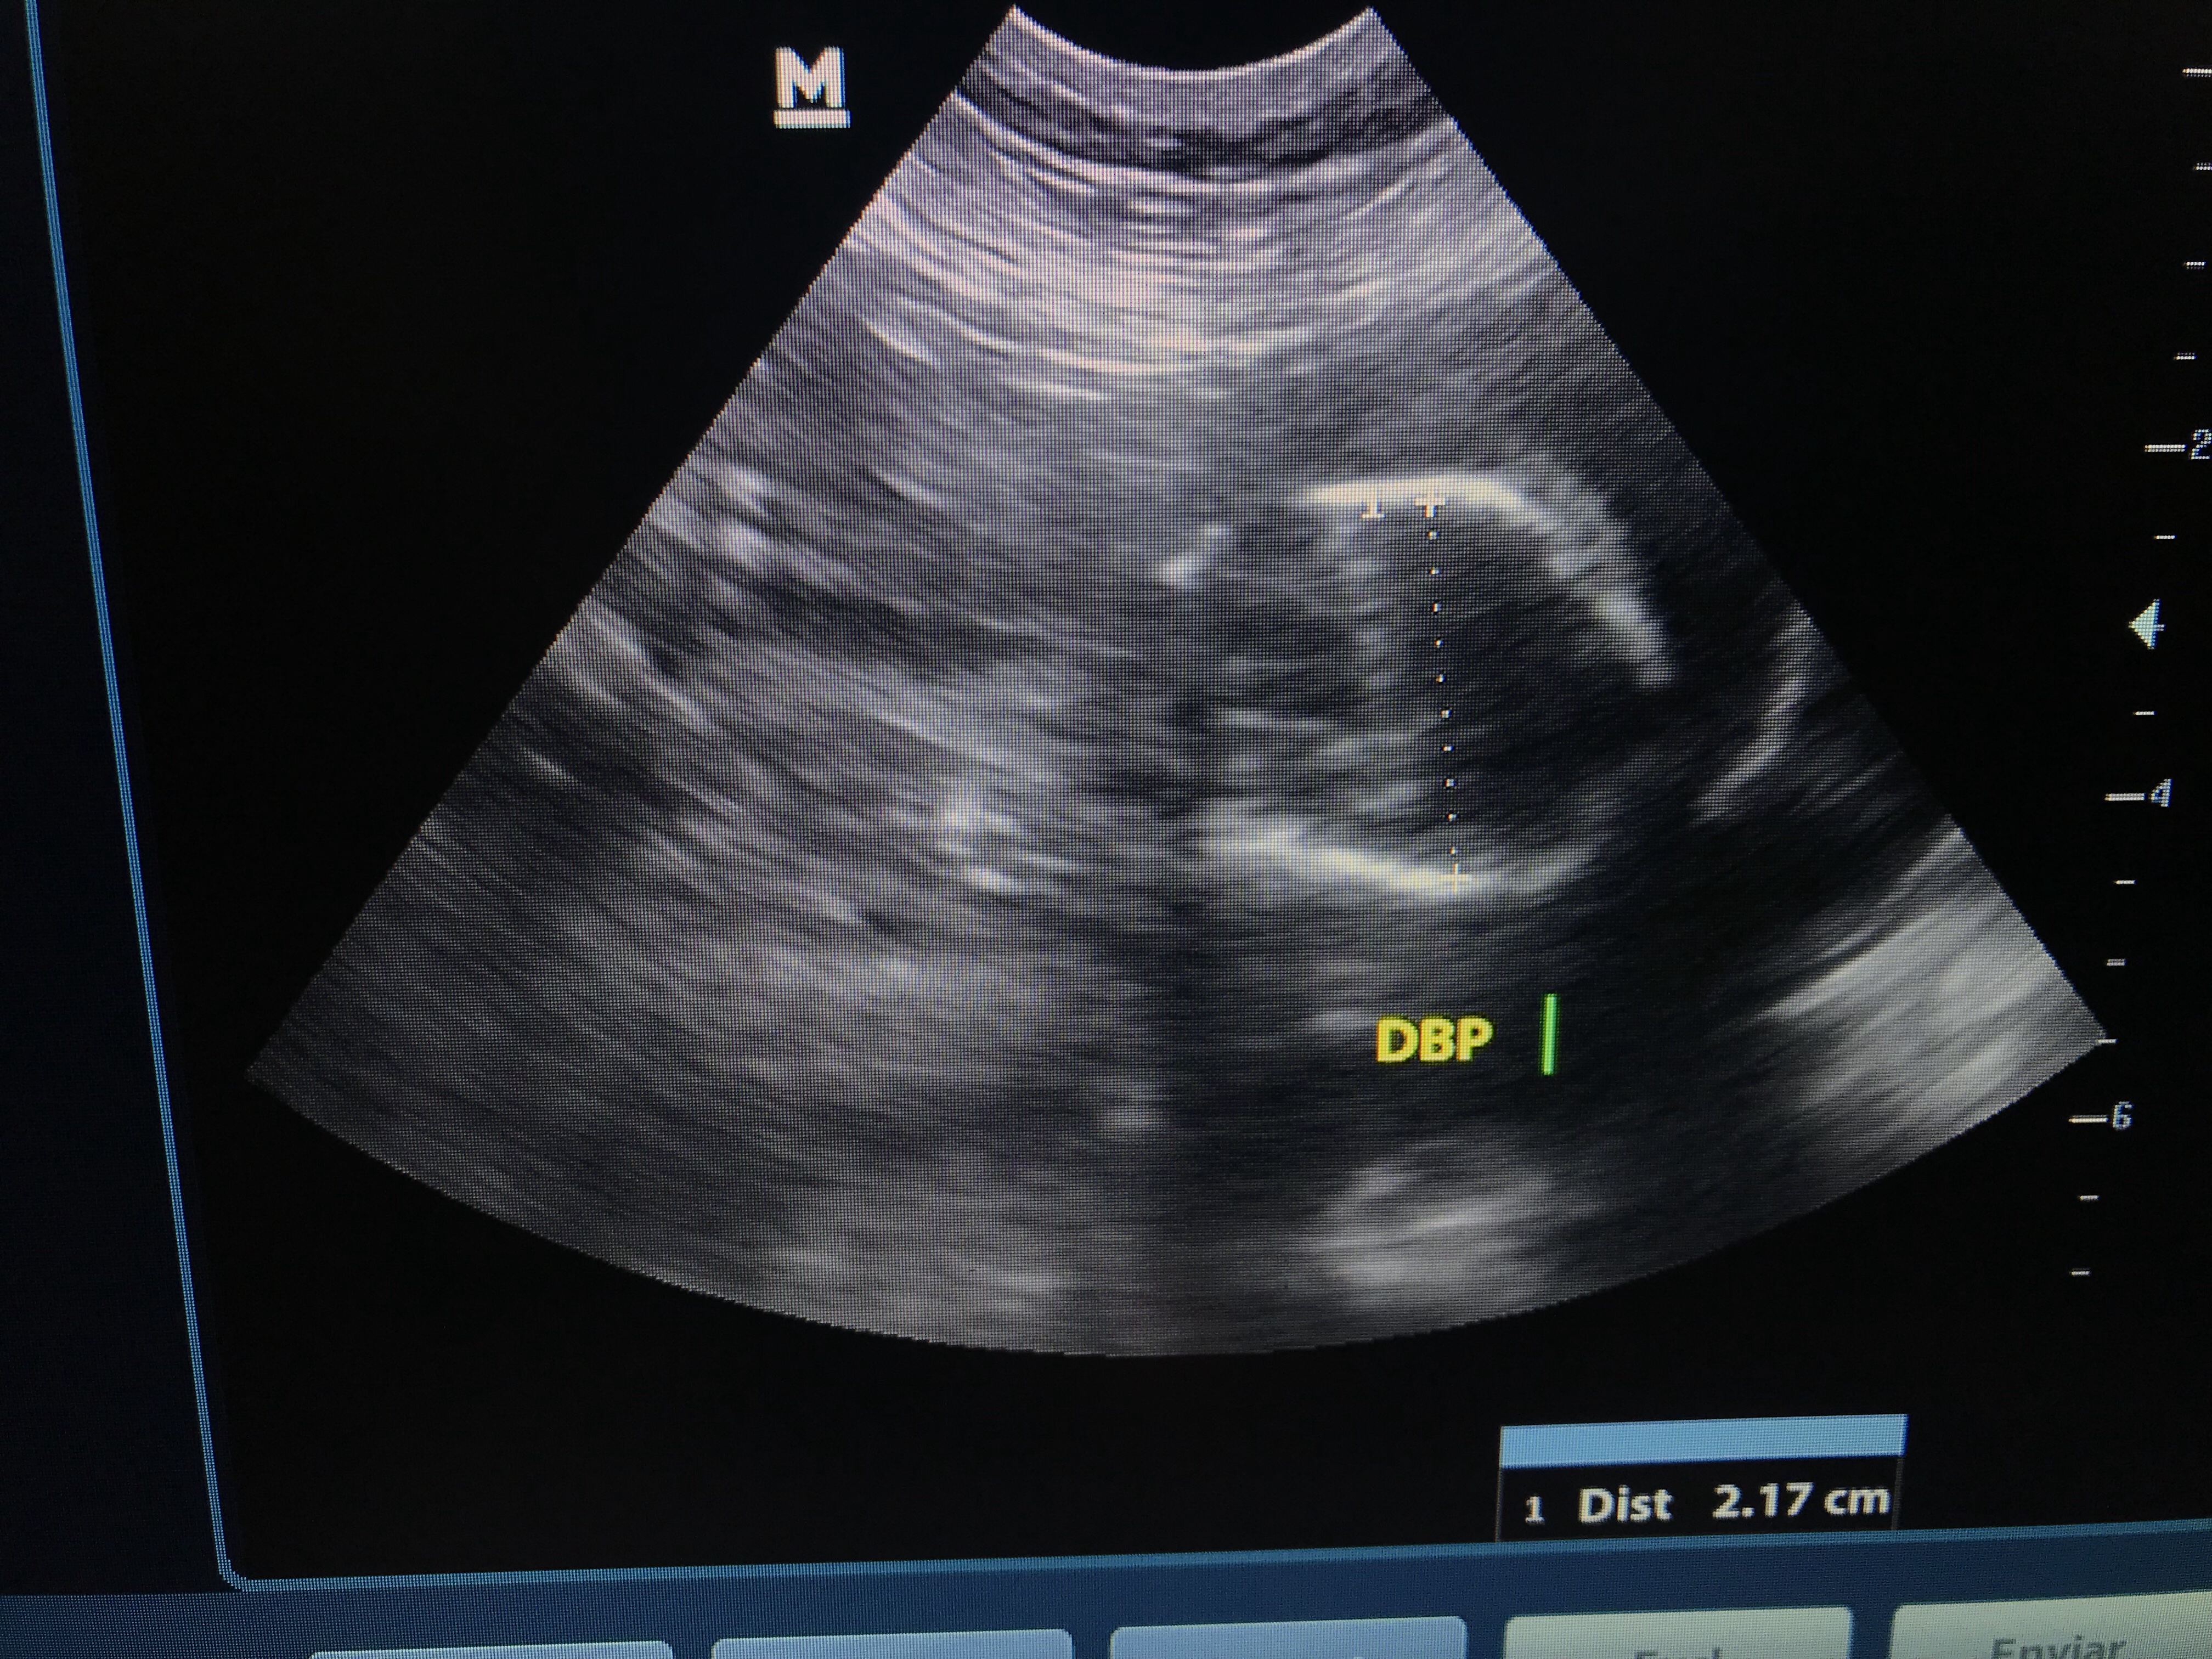

Foram 64 dias de espera e angústia de saber quantos filhotes, quais cores viriam, como seria o parto…

Dia 30/08/2018, depois de uma noite em claro com Maya em trabalho de parto sem evolução, cheguei às 6:30 na clínica e optamos pela cesárea.